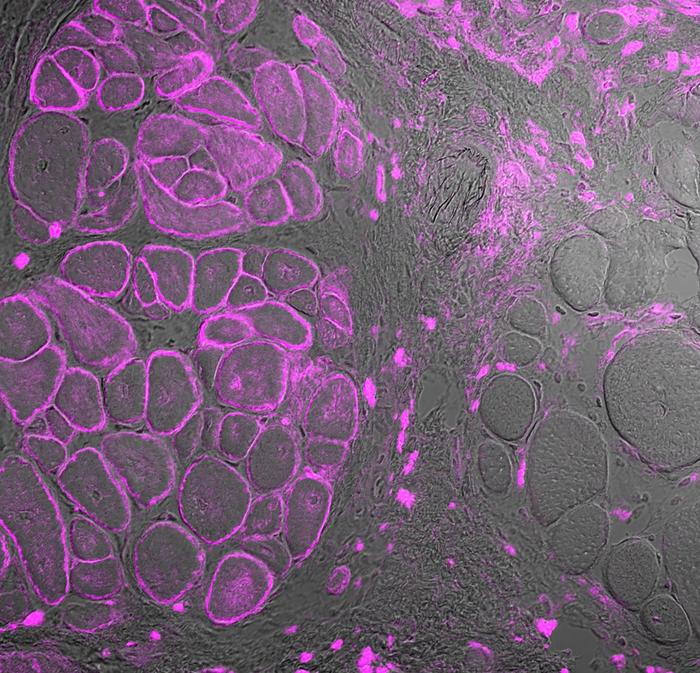

Professor Simone Spuler and her team led by Dr. Helena Escobar in the Myology Lab at ECRC have successfully removed muscle stem cells from two patients with limb-girdle muscular dystrophy, corrected the genetic error and restored functioning dysferlin proteins in cell culture. In new mouse models of the disease, they used the same process to collect cells, edit them and transplant the corrected cells back into mice, where protein function was restored and muscles began to regrow.

To fix the dysferlin mutation, Escobar uses CRISPR-Cas9, which is often described as “gene-editing scissors” and for which a Nobel Prize was awarded in 2020. The molecular scissors are guided to a precise location along a DNA molecule and then cut it, forcing the cell to repair the DNA. The aim is for the mutation to be corrected during the repair process, resulting in a properly functioning gene. The researchers tested their editing system in several cellular models all with very similar results: It worked with a high success rate and minimal unintended consequences.

“Even with these four changes, the generated protein is very similar in function to the wild type, which is the version we see in healthy individuals. It localized along damaged cell membranes and muscle was regenerated,” Escobar says.